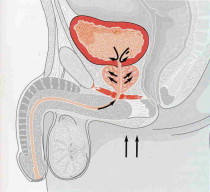

- Sitting or pressure on the perineum. Pressure may trigger mast cells.